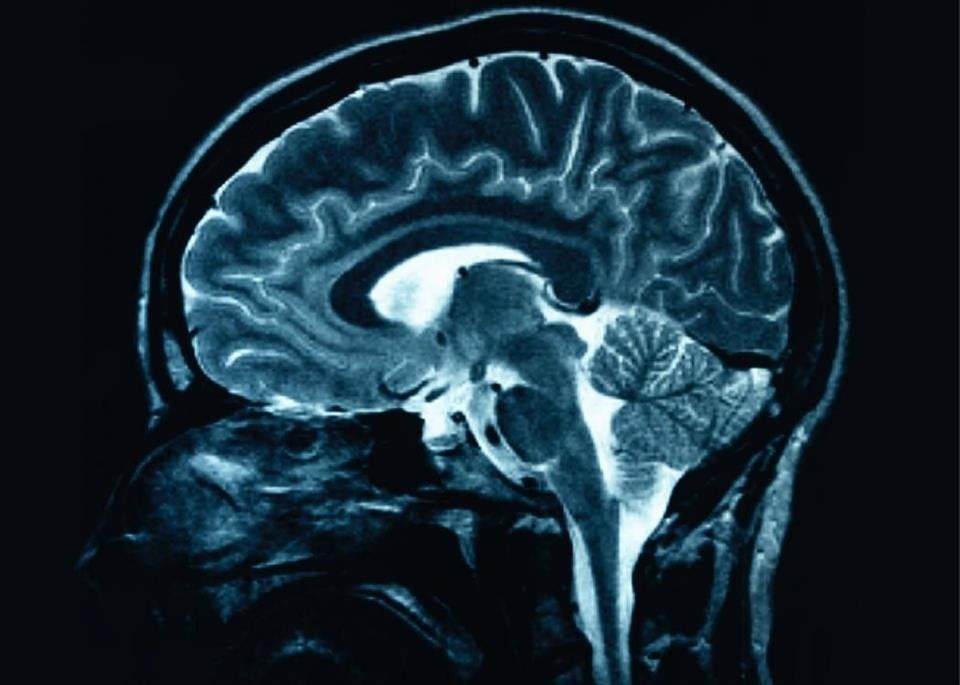

Por ejemplo, indicó, el virus que causa el resfriado común fue convertido en un tratamiento para el cáncer de cerebro en Estados Unidos. La enfermedad desapareció en algunos pacientes durante varios años, mientras que en otros se redujeron considerablemente los tumores.